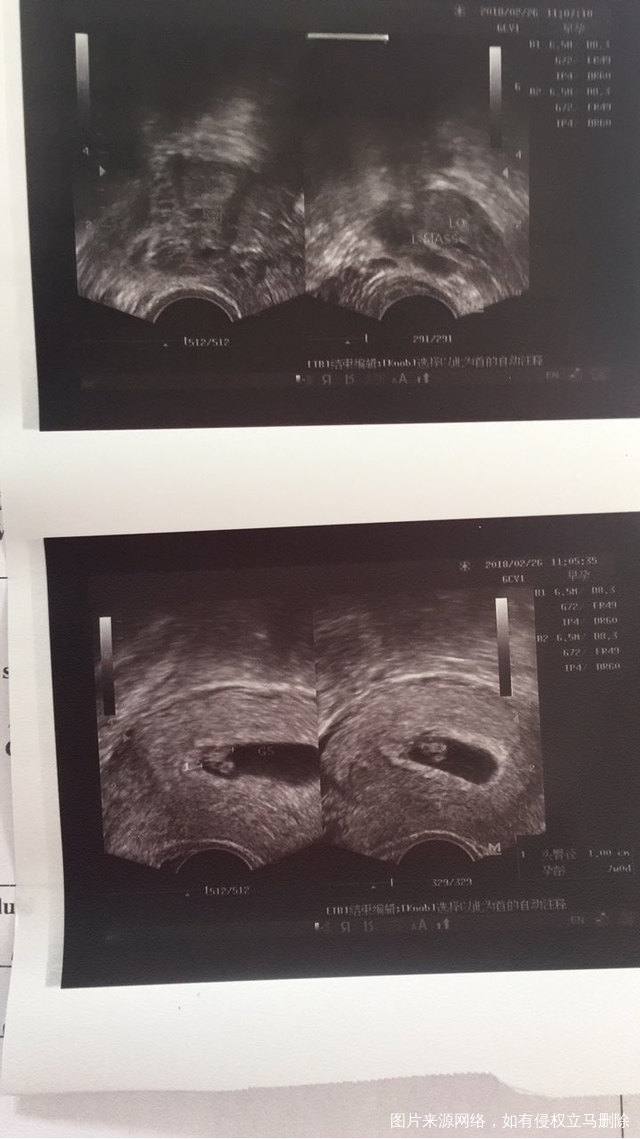

医生开的3.5一超 我反复的感冒咳嗽严重 今天去省妇幼看感冒 顺便提前做了B超 有胎心了 医生说49天了 眼泪哗啦哗啦的就流下来了 太不容易了 豆芽菜 你加油哦